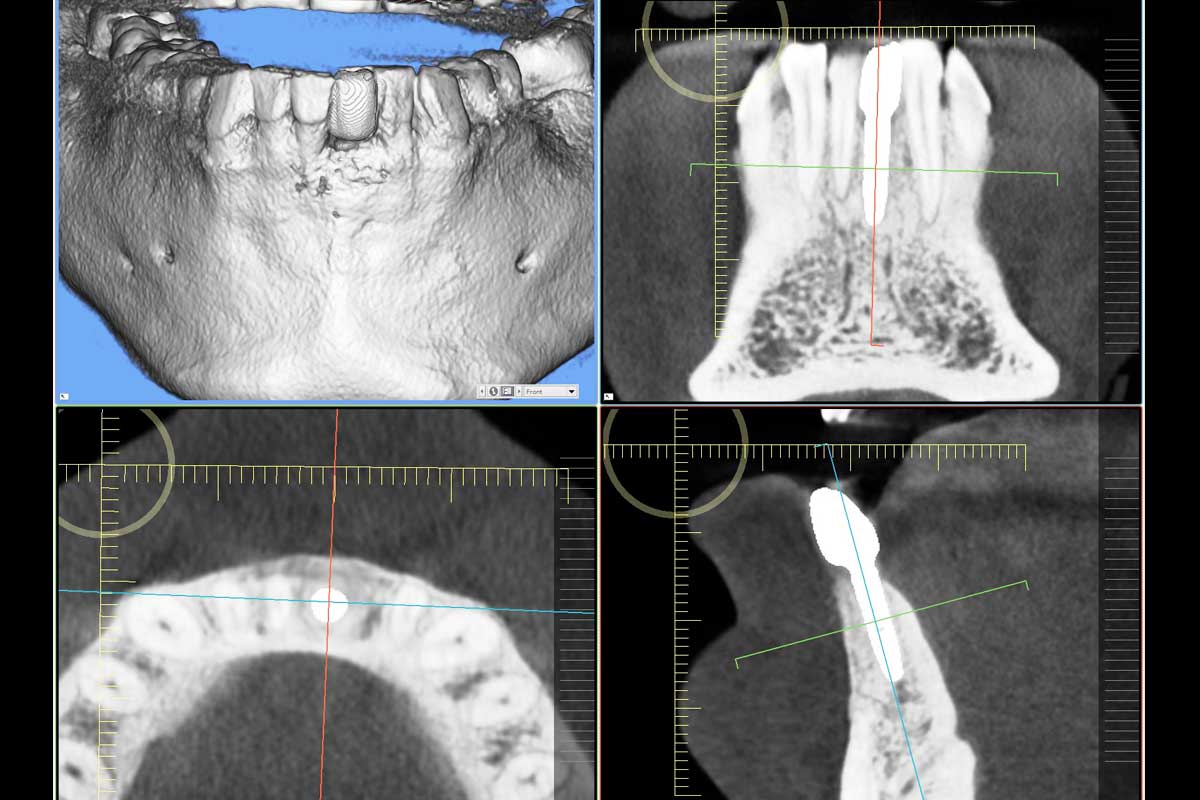

A patient presented with severe gingival recession and pronounced inflammation affecting tooth #24. Following extraction of the tooth and thorough debridement of the infected site, a complete loss of the vestibular wall and a slight resorption of the lingual wall were identified. In this situation, NOVAMag® membrane was cut to shape and given a suitable convexity and used as a rigid plate and fixated with two resorbable NOVAMag® fixation screws. The membrane was fixated of the lingual side only in this case. A narrow ⌀ 3.2 × 13 mm implant was placed. The remaining peri-implant gaps were filled with maxgraft® granules, and the augmentation site was finally covered with a collprotect® membrane.

Follow-up CBCT scans taken at 4 and 9 months demonstrated stable bone regeneration and preservation of the ridge contour in its natural form on the buccal side where the membrane was placed. Deeper placement of the implant initially would have been better. Satisfactory closure of the initial gingival recession was achieved despite minimal mucogingival intervention.